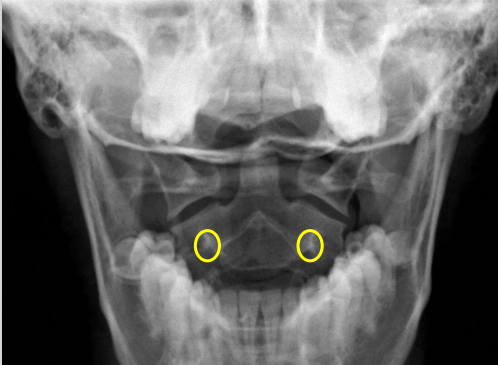

Uncinate processes

Inferior aspect of vertebral bodies

Junction of laminae

Pedicle shadows

Vertebral waist

Inferior endplate tips

Superior endplate tips

Disc spaces

End plate tips